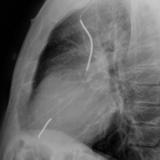

ICD Lat

Date: 04/25/2009

Views: 2727